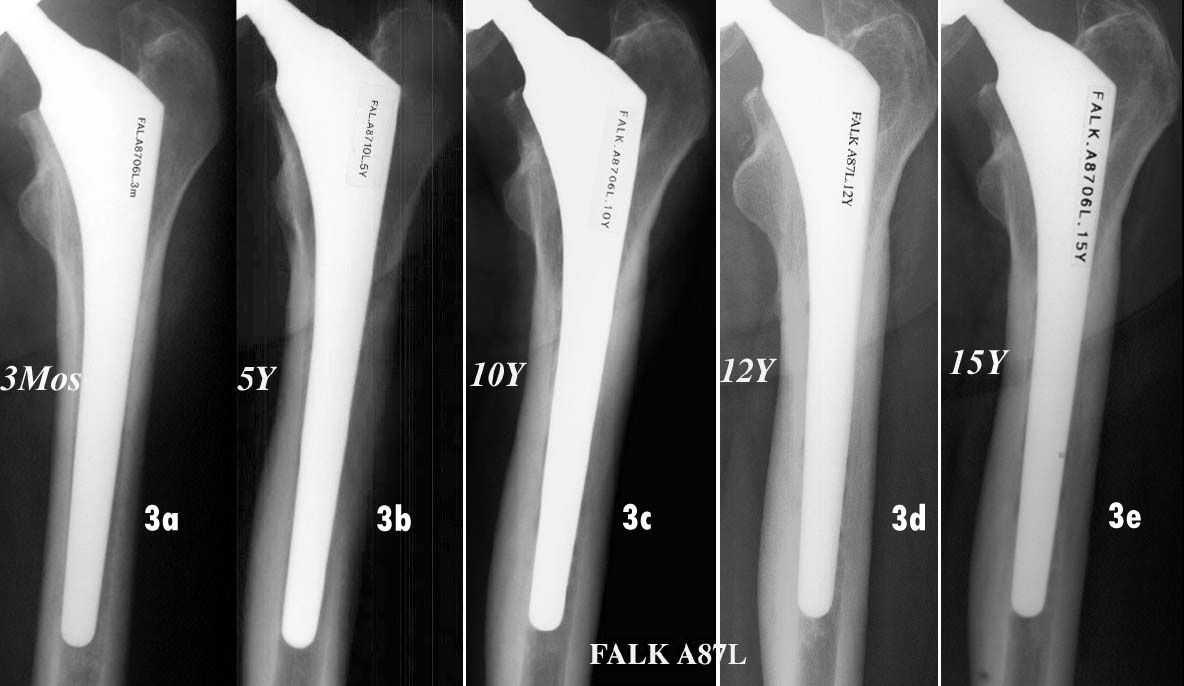

Over the years, the most salient feature remains the almost complete absence of any changes in the femoral region (Fig. 2). At last follow-up, with a total average score of 20.22/27 points (9–27; SD 4.93), neither of the two stem designs could be described as ‘unstable’ or ‘fibrous stable’ based on the Engh & Massin classification [29]. Using their criteria, bone growth was ‘suspected’ for 2.74% of cases and ‘confirmed’ for 97.26% of all cases at all follow-ups post 20 years. For the ARA prognostic score (femur), at last follow-up the average score was 5.03/6 and 43.3% of cases were rated 'excellent’ or ‘good’ compared to only 3.2% with a ‘poor’ or ‘bad’ prognosis [30].

Overall, these proximally HA-coated stems demonstrated excellent osteoapposition, optimal radiological fixation with bone growth in all cases, and no deterioration in outcomes even after 20 years. (Figs. 3, 4 & 5).